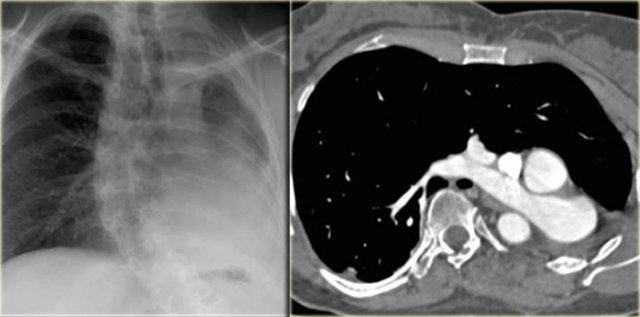

On the left a 2 month old boy with heart failure.

First study the image, then continue

The findings are:

- Large thymus which is normal for a 2 month old.

- Striking discrepancy between diameter of ascending and descending aorta.

The diagnosis is coarctation, which is nicely demonstrated on the posterior view of the reconstruction.

On the left two neonates with the pre-ductal type of coarctation.

The stenosis is in front of the left subclavia and there is arch hypoplasia.

Collaterals do not occur, probably because they don’t have time to develop.